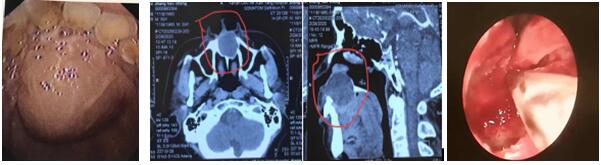

患者,男,59歲,因“發(fā)現(xiàn)口腔內(nèi)腫物3月”入院,腫物累及鼻底,并導(dǎo)致鼻底嚴重隆起,經(jīng)上頜骨CT三維重建檢查,腫物大,且口內(nèi)粘膜因腫物壓迫已很菲薄,還合并腎病綜合癥,口服激素一年余。住院后張立剛主任組織術(shù)前討論,認為患者如行傳統(tǒng)經(jīng)唇齦切口手術(shù)方式,極易導(dǎo)致傷口感染或不愈合,引起囗腔鼻腔漏,給患者帶來災(zāi)難性后果。經(jīng)查閱文獻,結(jié)合自身堅實的鼻內(nèi)鏡技術(shù)基礎(chǔ),決定行經(jīng)鼻內(nèi)鏡鼻底上頜骨囊腫摘除術(shù)。手術(shù)取鼻底小切口入路,切開黏膜后即見大量粘液溢出,清理后見口腔面黏膜菲薄,透光,與術(shù)前評估一致,遂將囊腫切除,等離子徹底止血,為防止壓迫導(dǎo)致口腔鼻腔漏形成,摒棄傳統(tǒng)的碘仿紗條壓迫兩周的觀念,術(shù)腔僅填塞可吸收明膠海棉,避免因填塞導(dǎo)致術(shù)后劇烈頭痛等不適。術(shù)后檢查見鼻腔結(jié)構(gòu)完整,口內(nèi)包塊明顯縮小,鼻面部無任何不適。

上頜骨囊腫在臨床上并不罕見,其發(fā)病隱弊,多無癥狀,當(dāng)發(fā)現(xiàn)上頜骨囊腫時,其上頜骨破壞程度已相當(dāng)嚴重。傳統(tǒng)手術(shù)方式創(chuàng)傷大,上頜骨骨質(zhì)暴露多,術(shù)后出現(xiàn)頭痛、流淚、面部腫脹及麻木,易增加感染機會。